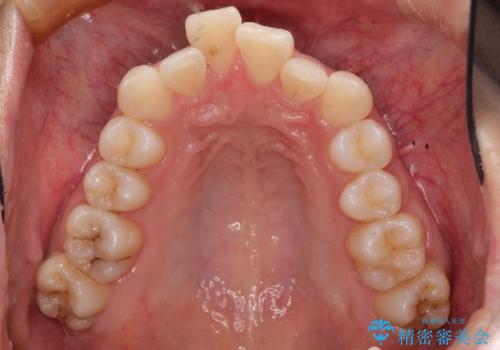

非抜歯で整える前歯の矯正

- 患者様は、前歯の重なり(叢生)が気になるとのことでご来院されました。診断の結果、奥歯を後方に移動することで前歯にスペースを確保し、非抜歯で歯列を整える方針としました。治療には審美性の高いホワイトワイヤーを使用し、奥歯の遠心移動にはリンガルアーチを装着しました。治療期間は約2年を予定し、月に一度の調整を通じて歯の動きを細かく管理しました。